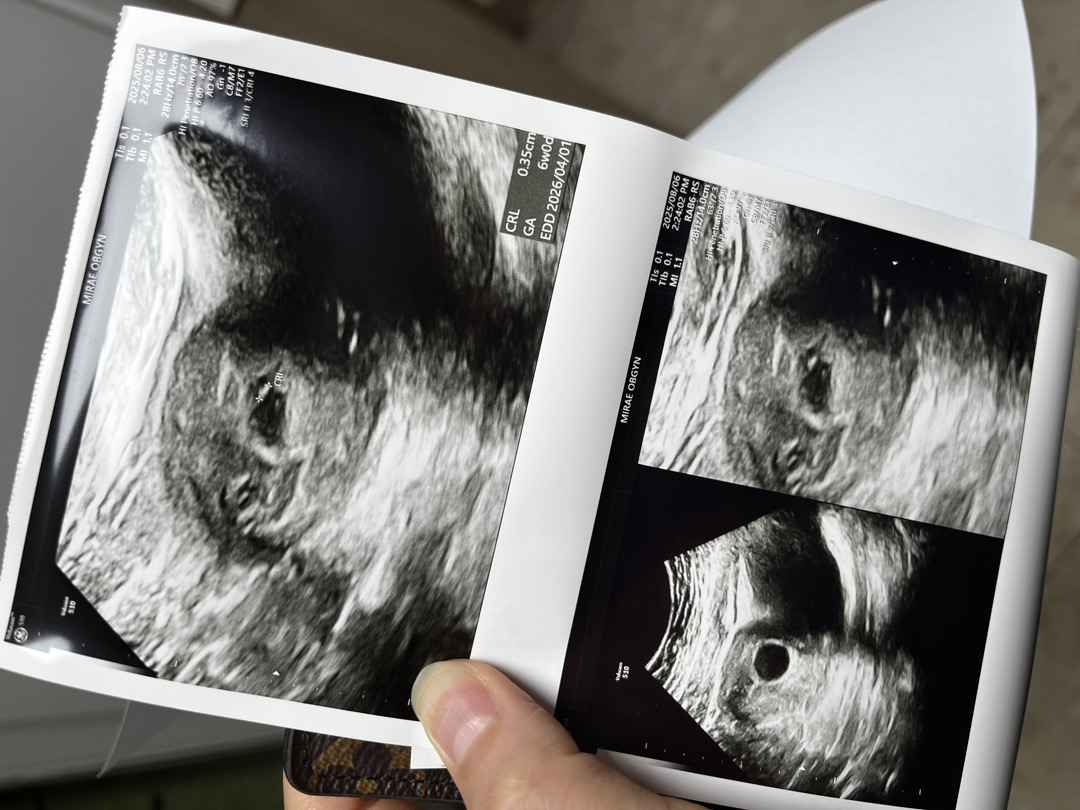

결혼식 앞두고 임신 확인!

내년 3월에 식장 잡아서 당겨야 할 거 같네요ㅠㅠ 미리 임신 계획은 있었는데 이렇게 빨리 올 줄은 몰랐네요! 아침에 테스트기 해보고 바로 병원가서 초음파 했더니 6주차라고... 애기집만 보일줄 알았는데 애기도 살짝 보인다고 의사샘이 신기해 하시면서 찍어주셨네요 ㅎㅎ 0.35cm지만... 원래 이때는 잘 안보이나봐요? 담주에 심장소리 들으러 갑니다~ 다들 홧팅이에요!